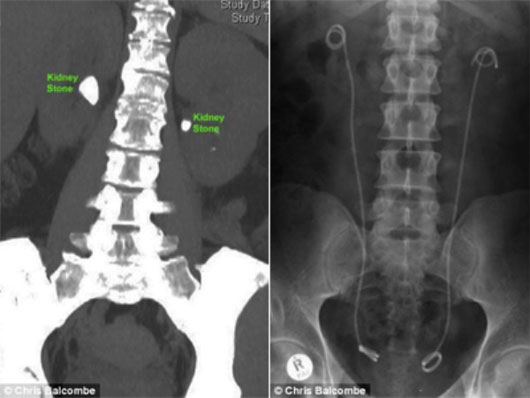

Hình ảnh vị trí các viên sỏi trước khi điều trị (trái) và cơ thể bệnh nhân đã hết sỏi (phải).

Kỹ thuật mới bao gồm việc dò tìm và định vị các viên sỏi bằng ống nội soi niệu quản trước khi sử dụng tia laser để tán sỏi. Tiếp theo, hai ống thông đặt trong thận sẽ dẫn lượng sỏi đã tán nhuyễn ra khỏi hai quả thận.